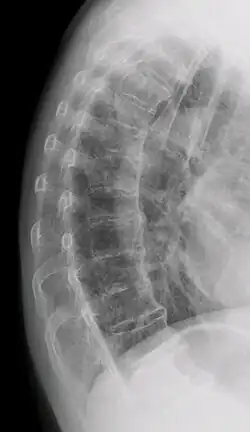

| DISH in an 80 year old female, also with T11 fracture. | |

Confluent ossification of multiple contiguous vertebral bodies in diffuse idiopathic skeletal hyperostosis (DISH)